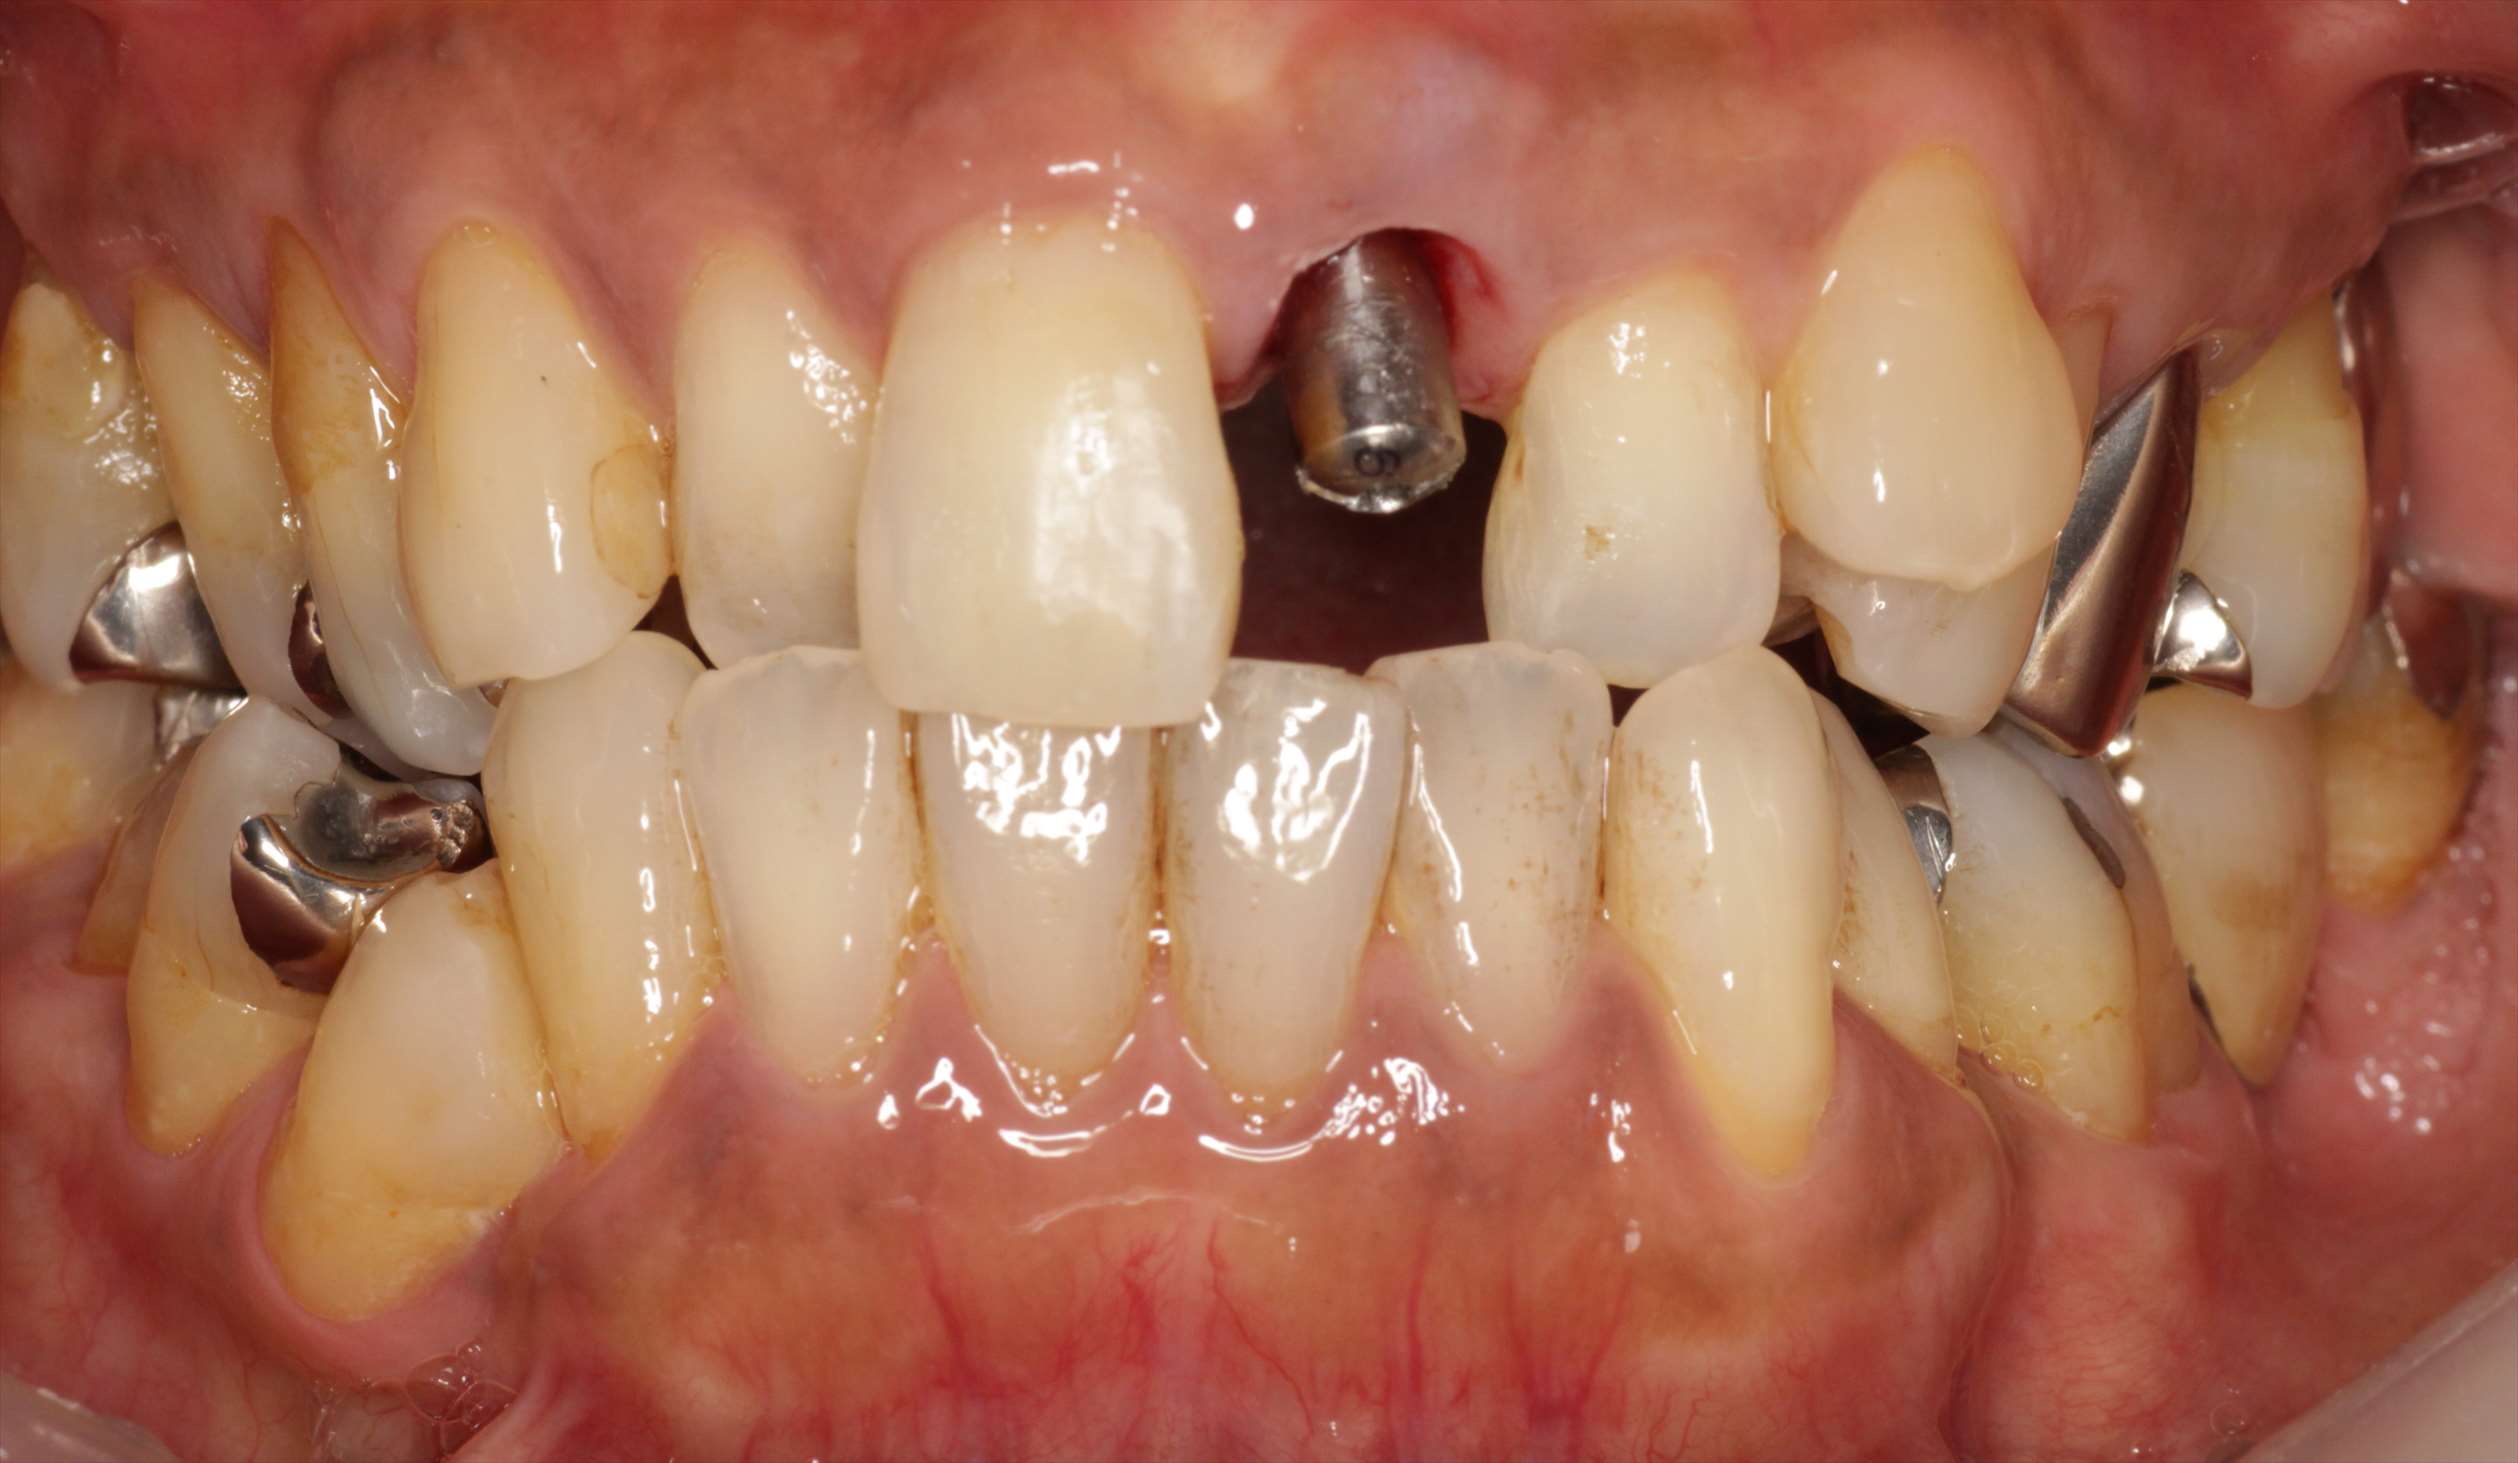

抜歯した左上1番の歯です。

抜歯即時でインプラントを埋入。

その後、THAを装着した状態です。

インプラント埋入当日に仮歯を入れた状態です。